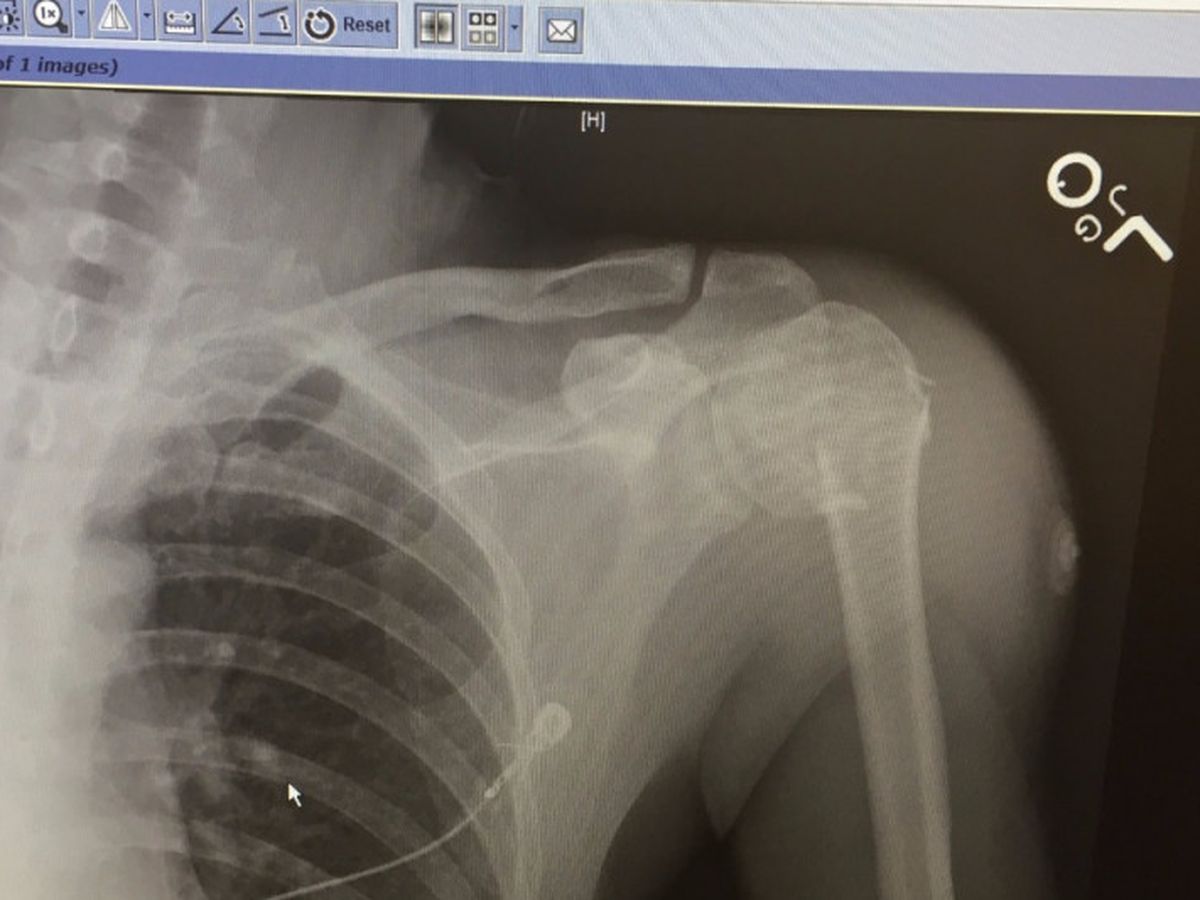

When hurricane Irma hit and we came home that first day. The first thing we saw was the ceiling in the house had fallen in several spots from a tree and rain that had hit the roof during the hurricane. We knew we didnt have the thousands of dollars to pay someone to fix it. So my husband who has worked on a few roofs in his day said ill do it. Ill fix the house for us. He was doing such an amazing job. He got the ceiling back up in our youngest roof and patched the bathroom where it had fallen as well. Pulled the broken wood off the roof and cut and replaced it. Pulled half of the old roof up and started to add the layers. In the process of fixing the roof, he got offered a job at the airport which has been his dream since he was a kid and he got so excited. He would get to be doing something he loved. So last Thursday 21st the ladder he was on gave way and he fell 12 feet onto concrete below. He broke his arm where it attaches to his shoulder and will be having surgery this Wednesday. So we have a new set of problems. He wont be bringing in any income for the next eight to nine weeks and we have all the supplies and a half-finished roof for our family. I know the lord gives us what we can handle and i guess he thinks we can handle a lot. Im looking for any help. If someone knows someone who would be willing to come and help fix the roof or financial to help keepwhilisnt working. surgery. and goo and thoughts are also very much needed. You Got him pre registered at the hospitialof prayer can do to help someone.